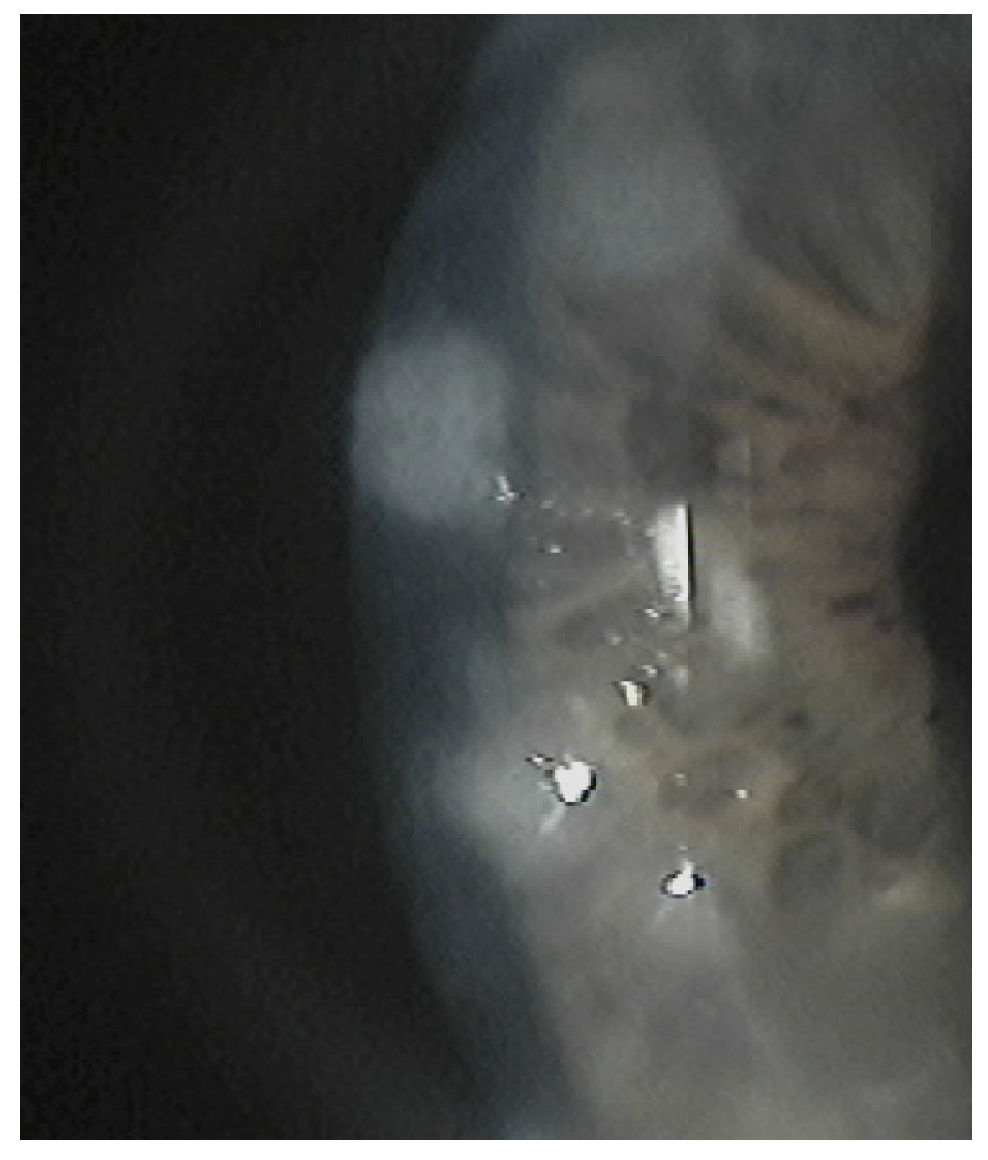

5. Clinical Signs and Symptoms

The subepithelial elevated nodules of the disease are gray-white or blue-white, and they often present in a roughly circular configuration involving the central or paracentral cornea. The nodules are typically separated by a clear cornea and are localized in the mid-periphery, and there may be only one or up to eight of them, and the nodules might be confluentin advanced stages.(Figure 1 and Figure 2). In some cases, the nodules are localized in the central cornea. This condition occurs in association with dry eye or long-standing keratitis (e.g., phlyctenulosis, trachoma, and interstitial keratitis), and the degeneration may not appear until years after the active keratitis has subsided. In extensive CL wearers, typical nodular localization at 3 and 9 o’clock has been described [5]. In about 60–68% of patients, there have been reports of symptoms such as pain, foreign body sensation, tearing and relapses in corneal erosions. In advanced stages, the most common presenting symptom is decreased visual acuity, and this is due to induced irregular astigmatism with hyperopic shift.

Figure 1. A single nodule.